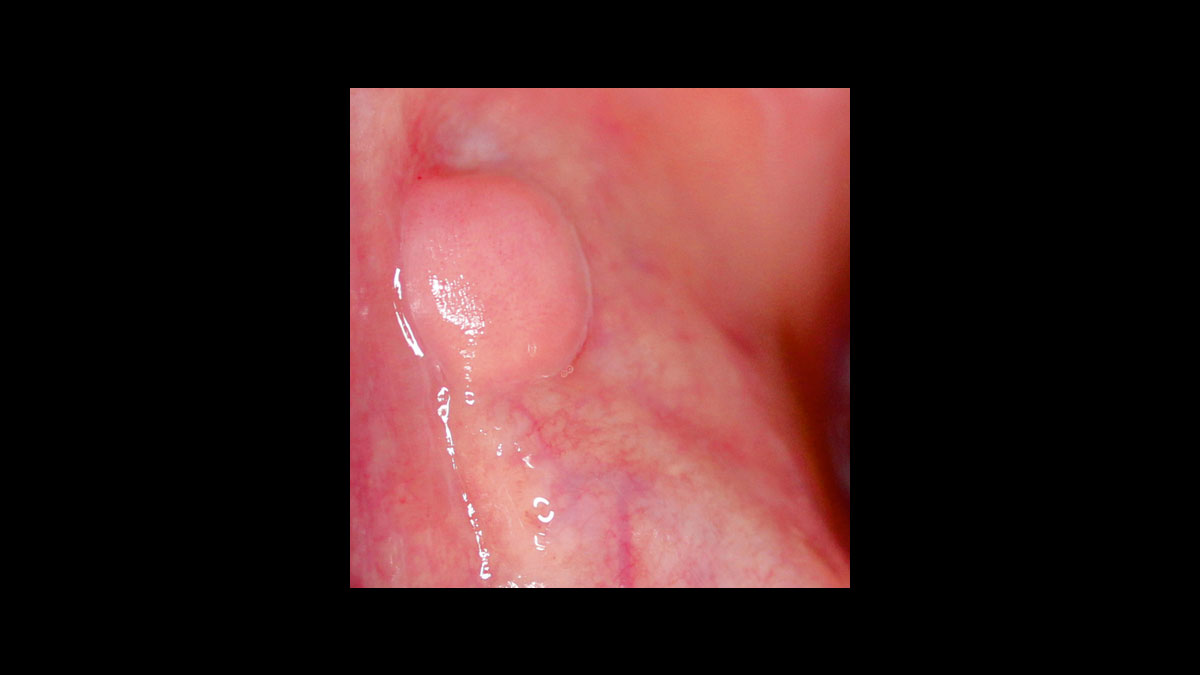

• Épulis